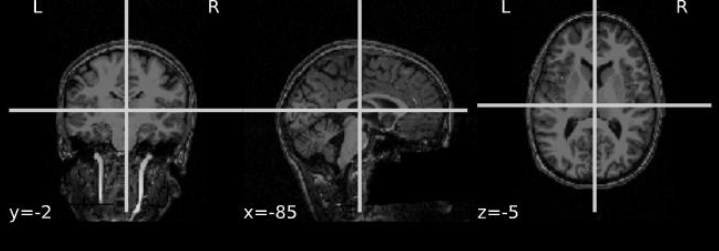

The PPMI dataset contains MRI images of patients in DICOM (Digital Imaging and Communications in Medicine) format files [50], which represents a two-dimensional image of a single angle of the person; therefore, the first step of the pre-processing was the reconstruction in a three-dimensional format, or in NIfTI (Neuroimaging Informatics Technology Initiative) [74], a format notoriously used in the medical field. Fig 4(a) shows the original DICOM format of an MRI belonging to PPMI visualized by using the tool “MicroDicom” [36], while Fig. 5(b) shows the three-dimensional NIfTI format if the same image produced by the “MRIcroGL”[70] tool.

Refer to caption

Figure 4: MircroDicom interface

Figure 5: MRIcroGL interface